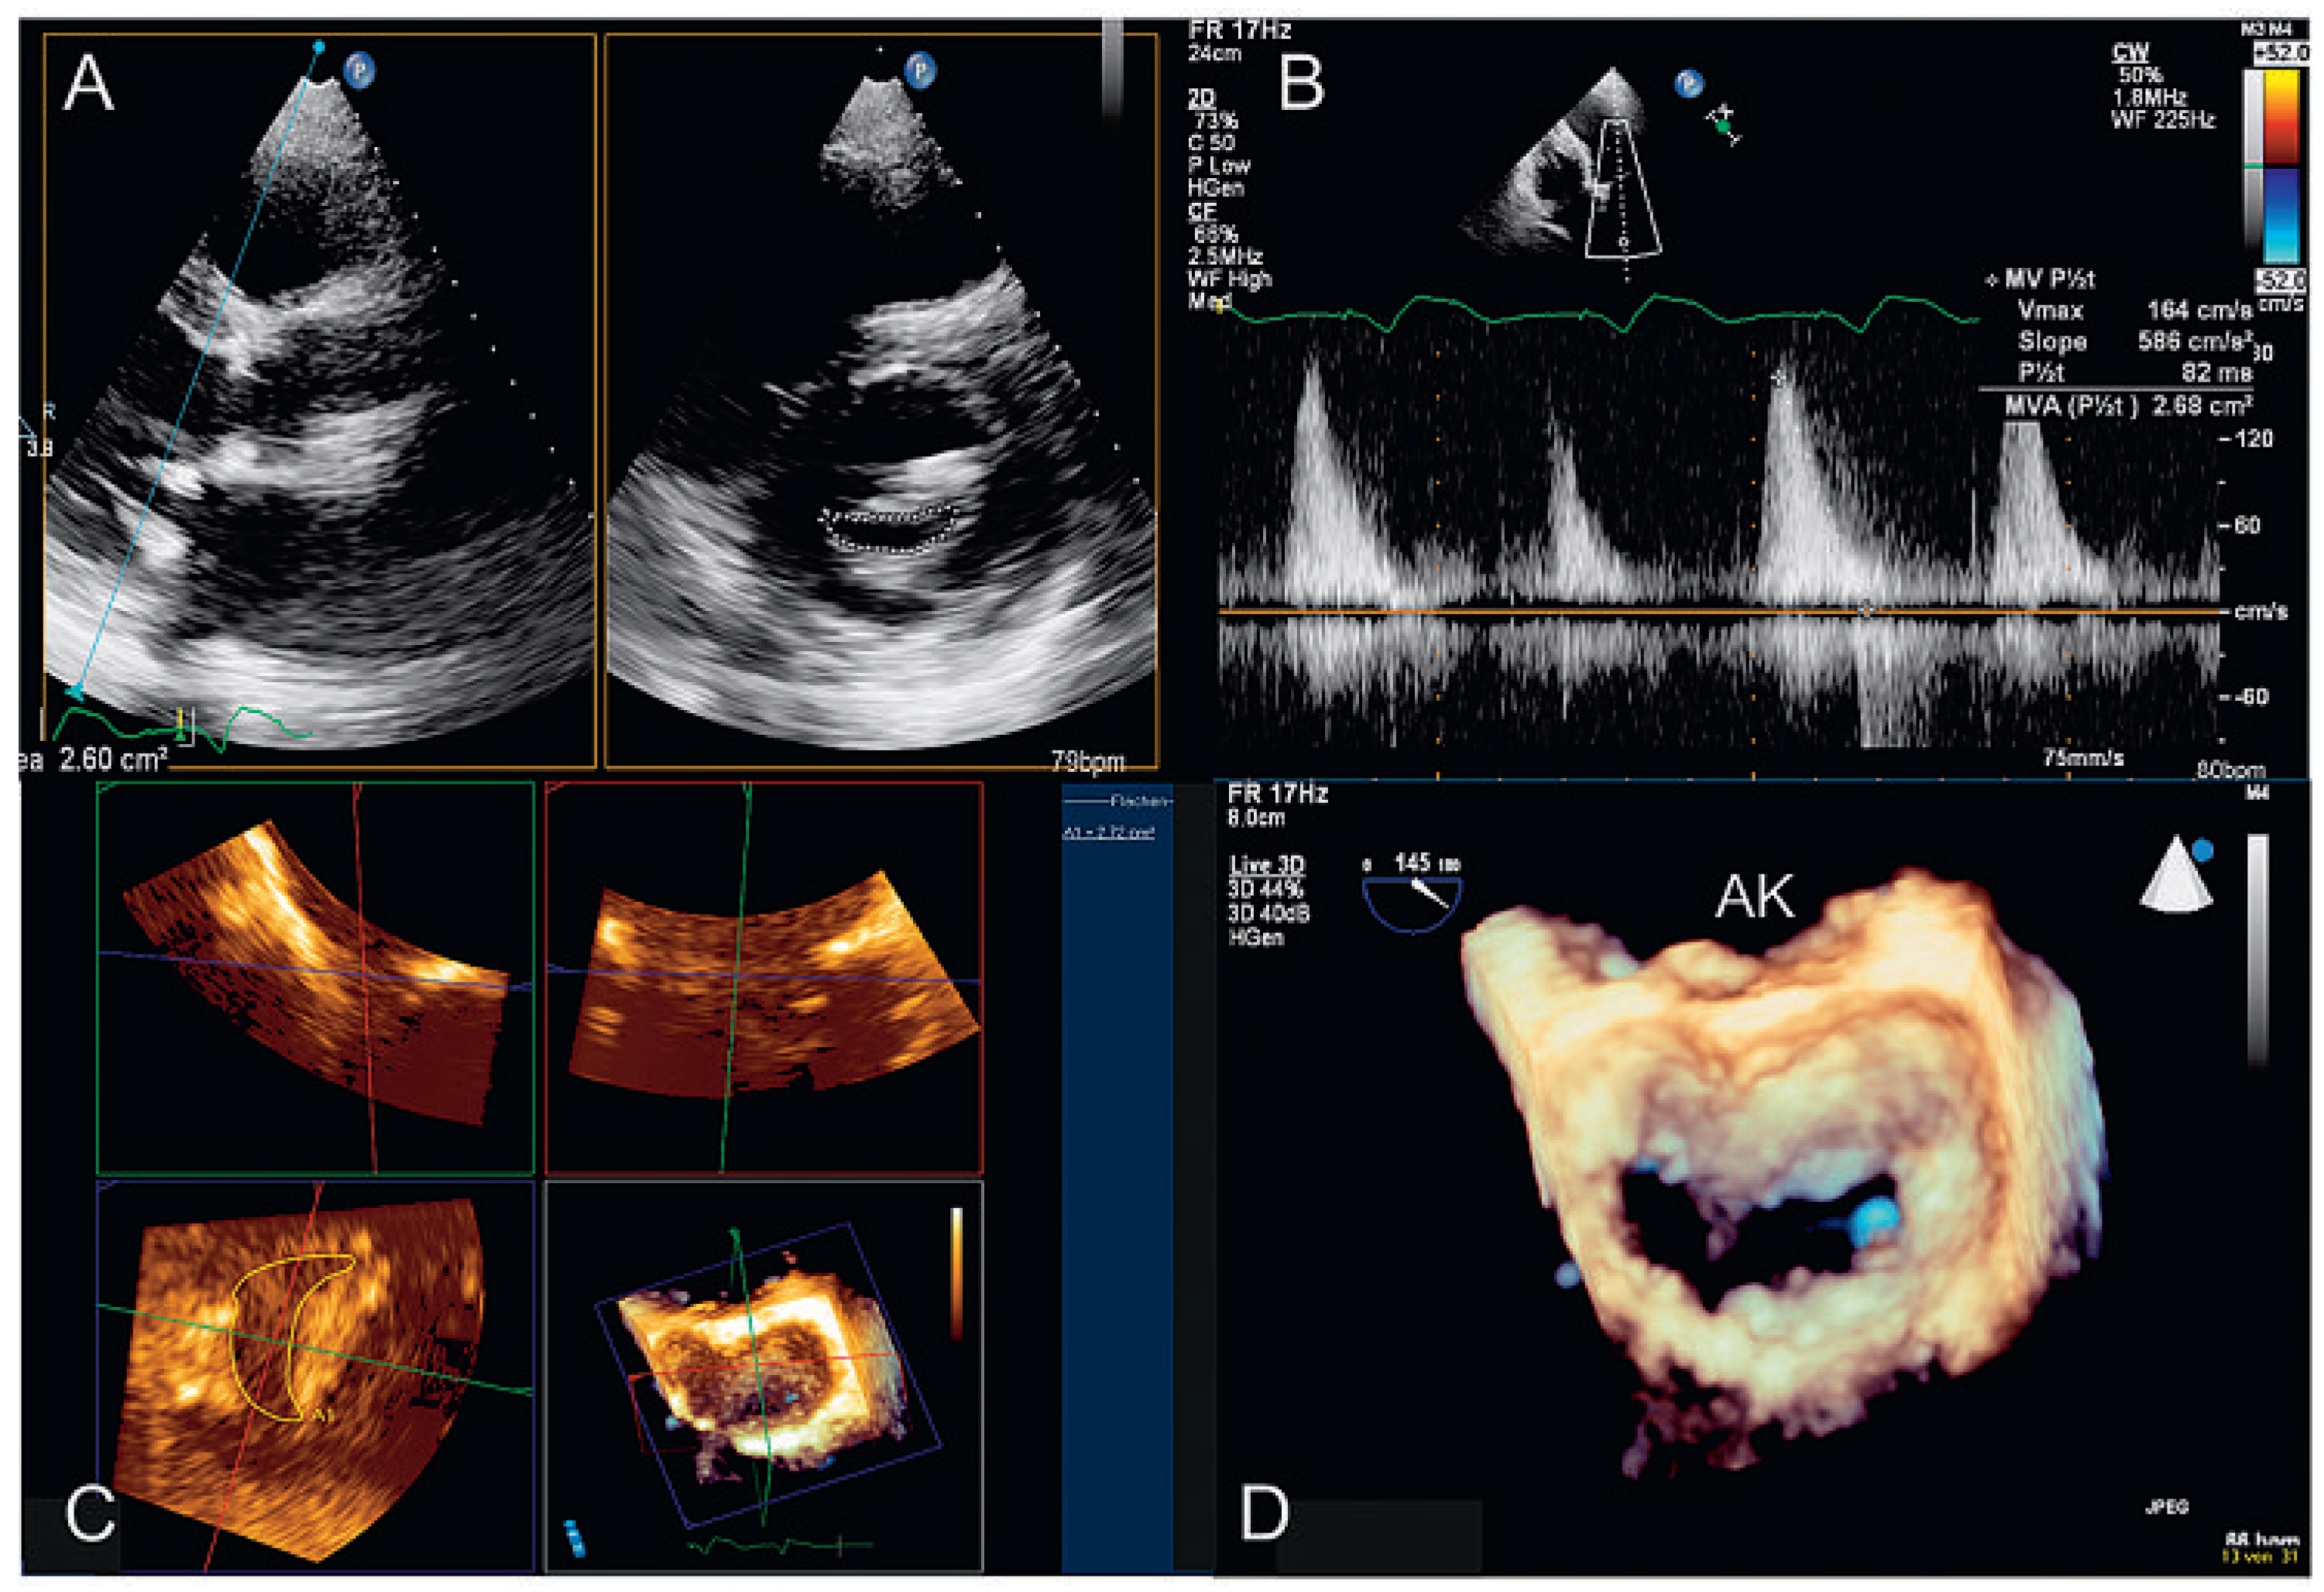

3DE zur Beurteilung der Nativklappe

3D-TTE